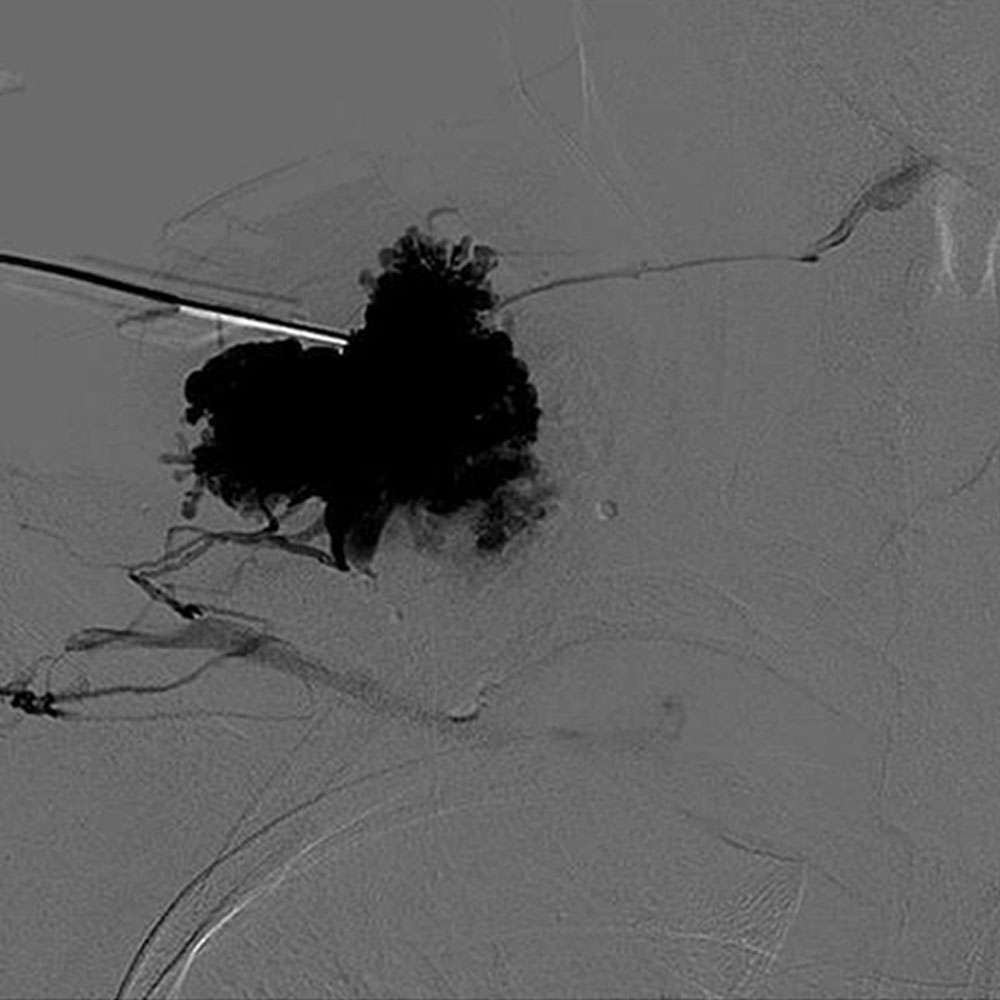

Ascending phlebography is used to clarify aplasia and dysplasia of the deep venous system when duplex sonography and MRI do not provide a reliable assessment. The indication is therefore limited to very specific questions. It is during sclerotherapy of a venous malformation that  phlebographic imaging by direct puncture is essential.